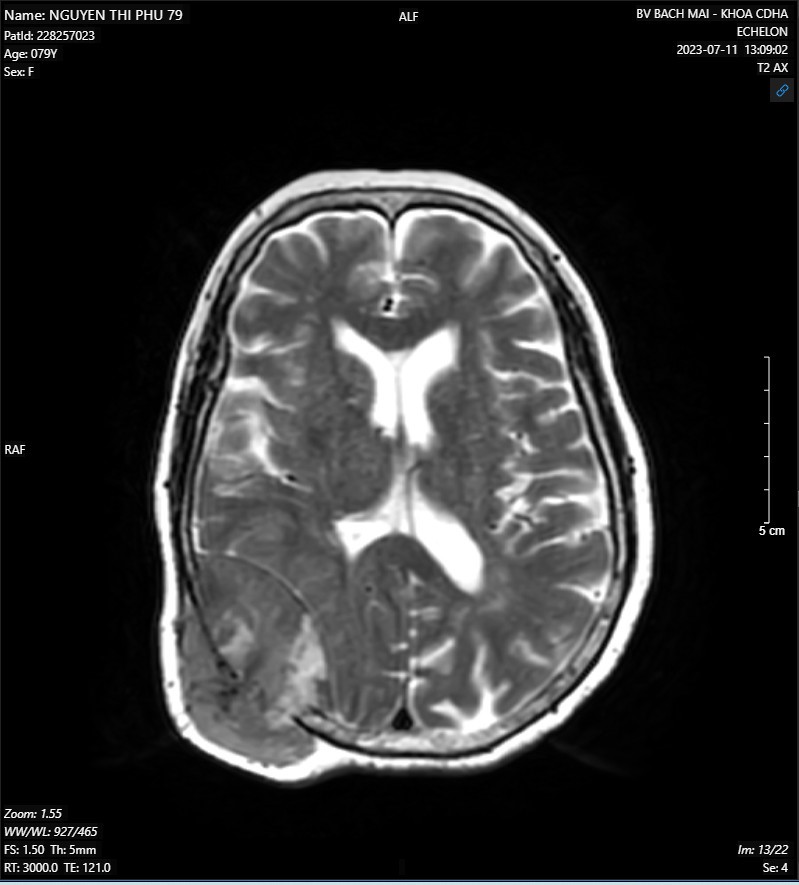

- MRI não-mạch não có tiêm thuốc đối quang từ:

Hình ảnh khối ngoài trục vùng thái dương-chẩm phải kích thước 48x50x60mm nghĩ nhiều đến khối u xương, có chảy máu trong u, gây tiêu xương sọ và xâm lấn phần mềm

Hình 2. Hình ảnh MRI não-mạch não có tiêm thuốc đối quang từ.